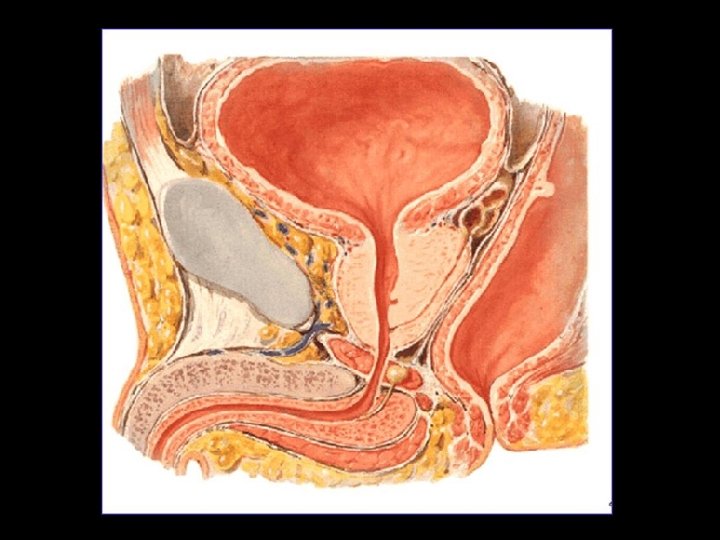

Ureterorragia = Trauma uretral? Estudio dirigido!

Extravasación del contraste con disrupción de la uretra membranosa posterior Compromiso parcial del diafragma urogenital.

Determinar sitio de disrupción/ruptura Compromiso vejiga? Ver: extravasación Fracturas de pelvis + frec hombres Tipo 3 injurias posterior 20% afectacion vejiga

TIPO 1 Estiramiento posterior de la uretra. Diastasis del pubis. TIPO 2 Ruptura de uretra posterior por debajo de diafragma (sin lesión)

TIPO 3 Ruptura uretra posterior y diafragma. extravasación por uretra membranosa. TIPO 4 Contraste extraperitoneal. Ruptura de vejiga. Hematoma perivesical Distasis de pubis